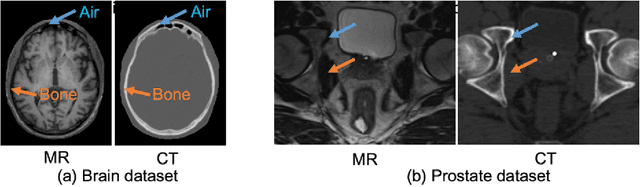

Abstract:Recently, more and more attention is drawn to the field of medical image synthesis across modalities. Among them, the synthesis of computed tomography (CT) image from T1-weighted magnetic resonance (MR) image is of great importance, although the mapping between them is highly complex due to large gaps of appearances of the two modalities. In this work, we aim to tackle this MR-to-CT synthesis by a novel deep embedding convolutional neural network (DECNN). Specifically, we generate the feature maps from MR images, and then transform these feature maps forward through convolutional layers in the network. We can further compute a tentative CT synthesis from the midway of the flow of feature maps, and then embed this tentative CT synthesis back to the feature maps. This embedding operation results in better feature maps, which are further transformed forward in DECNN. After repeat-ing this embedding procedure for several times in the network, we can eventually synthesize a final CT image in the end of the DECNN. We have validated our proposed method on both brain and prostate datasets, by also compar-ing with the state-of-the-art methods. Experimental results suggest that our DECNN (with repeated embedding op-erations) demonstrates its superior performances, in terms of both the perceptive quality of the synthesized CT image and the run-time cost for synthesizing a CT image.